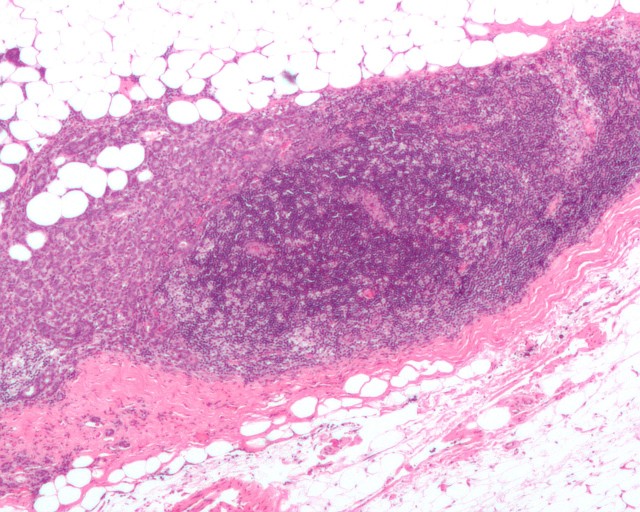

乳腺癌侵犯淋巴管